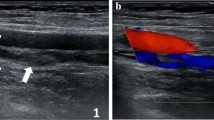

A clinically suspected DVT, often based on a positive D-dimer test and clinical scoring systems, is evaluated and followed up by compression ultrasound (CUS), now considered the standard diagnostic imaging test for lower limb DVT for the popliteal vein and above [5–8]. An acute symptomatic DVT is confirmed by CUS through the lack of compressibility of the common femoral, femoral and/or popliteal veins. However, the clinical presentation and diagnosis can be complicated by often ill-defined and occasionally absent symptoms that may accompany thrombus formation. In addition, many patients do not undergo follow-up imaging to confirm whether the affected vessels have fully or partially recanalised or remain occluded with chronic organized thrombus and increased collateral venous flow providing venous return.

Compression ultrasound has proven to be a simple, non-invasive, highly accurate, safe and cost-effective technique with high sensitivity and specificity of 89–100 % and 87–100 %, respectively, for DVT of the popliteal vein and above in symptomatic patients [4, 9]. Despite all its advantages, CUS cannot reliably determine the age of a thrombus and thus distinguish an acute recurrent DVT from a persisting previous thrombus in the same location. Interpretation of CUS findings is further complicated by the persistence of US abnormalities after the initial episode (80 % of patients after 3 months and 50 % of patients after 1 year from initial DVT diagnosis) [4, 7, 10, 11]. Quantitative thrombus measurements have been proposed as a way to distinguish between new and recurrent DVT that, although with poor interobserver agreement in initial studies, have improved in recent publications [12, 13]. However, limited information remains available on the temporal evolution of an acute thrombus and our ability to distinguish between a resolving (old) or recurring (new) DVT.